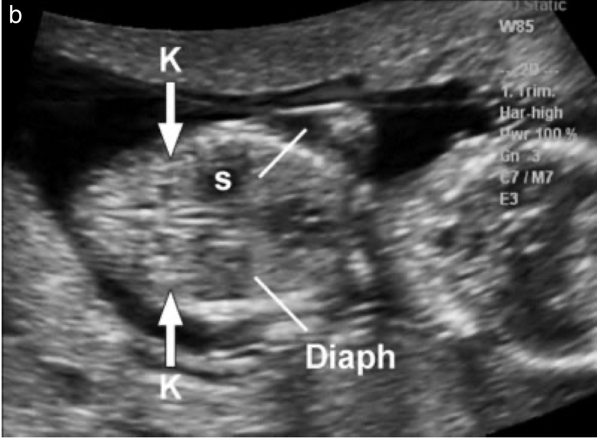

In the period 11-13 6/7 weeks, the stomach and bladder can be visualized, which is the empty echogenic structure in the abdomen. The fetal stomach is located on the left side, the intestines are in the abdomen and the umbilical cord is inserted into the abdominal wall. The fetal kidney is located next to the spine, has a structure resembling a pea.

| Figure 6. Stomach and 2 kidneys of fetus |